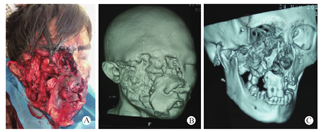

患者男,39岁,云南普洱人,上山采蜂蜜时被黑熊袭击,致右侧颜面部严重毁损,大面积皮肤软组织缺损,右侧颧骨颧弓缺损,右颊部贯通伤,右侧腮腺及眼睑缺损,眼球损伤。于当地医院急诊行清创包扎、气管切开、补液及抗感染支持治疗,受伤40 h后于2016年11月转入昆明医科大学第二附属医院整形外科,术前完善相关检查,并行颌面部CT三维重建(图1)。本研究参考了赫尔率基宣言。患者知情同意。